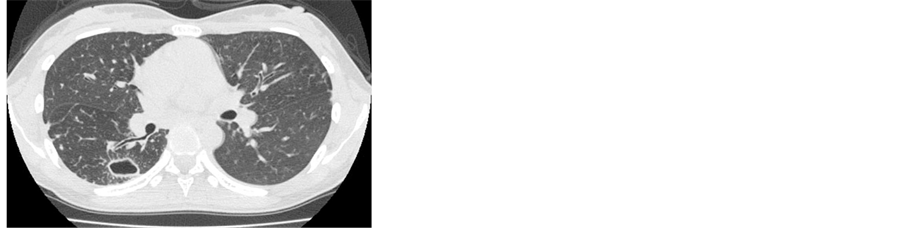

Case 2: A 33-year-old woman visited our hospital complaining of productive cough and general fatigue. She had no underlying diseases and no smoking history. There were no abnormal physical findings on admission. There were no abnormal laboratory findings except for the elevation of C-reactive protein (CRP 0.34 mg/dl, normal range: <0.30 mg/dl). Although TST was not performed, QFT-G was negative (<0.05 IU/ml). Chest radiographs showed linear shadows in the right upper lung field and cavity lesions in the right upper and lower lung fields (Figure 3). Chest CT showed several cavities surrounding the infiltration shadow and satellite lesions with bronchiectasis in the right upper and lower lobes (Figure 4). The culture of expectorated sputum generated

acid-fast bacilli several times and the result of DDH method identified M. kansasii. Finally, she was diagnosed with pulmonary M. kansasii disease based on the diagnostic criteria of the ATS guidelines [7] . She was treated with combined chemotherapy using

Figure 4. Chest CT showed several cavities surrounding the infiltration shadow and satellite lesions with bronchiectasis in the right upper and lower lobes.

INH, RFP, and EB for one year and clinical symptoms and abnormal chest shadows improved following the combined chemotherapy.